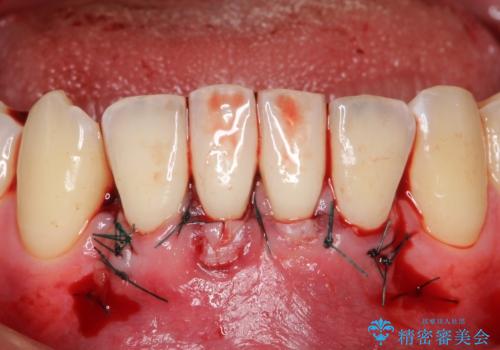

下顎前歯の歯肉退縮 結合組織を用いた根面被覆

- 歯肉退縮を主訴に来院された患者様です。

口蓋から結合組織を採取して、根面被覆を行いました。

十分な根面被覆を達成で患者様にも満足していただけました。

手術後は3日~1週間ほど痛むことが一般的です。